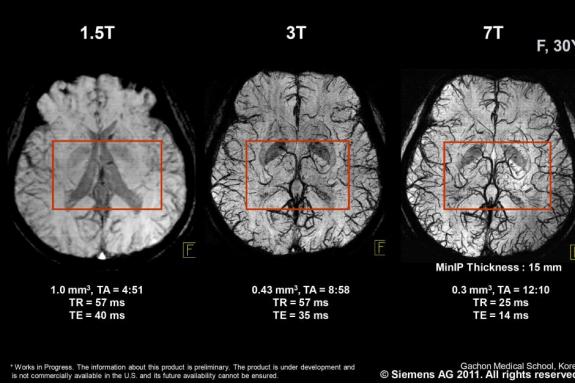

Зигфрид  Траттниг,  врач,  профессор,  основатель  и  председатель магнитно­резонансного  научно­инновационного  центра  (MR  Center  of Excellence  –  MRCE  в  Вене,  Австрия)  считает,  что  7Т  –  это  будущее, благодаря  превосходному  соотношению  сигнал­шум,  спектрального  и пространственного разрешения по сравнению с 1,5 Т и 3 Т системами.

Несмотря  на  то,  что  относительно  мало  научных  исследований намеренно  сравнивали  1,5Т,  3Т  и  7Т,  важно  помнить,  что  высокая напряженность  поля  не  гарантирует  лучшей  диагностической  точности  для всех видов аномалий и заболеваний. Это значит, что 7 Т МРТ занимает узкое место  на  рынке  для  определенных  режимов  и  методов  визуализации.  Они включают 31Р МР спектроскопию (31Р­МРС), которую можно применять как неинвазивный  метод  для  измерения  относительных  внутриклеточных концентраций нескольких фосфорных метаболитов в различных органах.